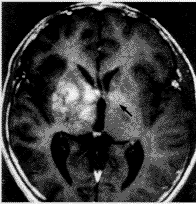

二、囊变、坏死与出血: 11例中5例肿瘤内可见囊变、坏死灶。CT图像上表现为水样低密度影(图1,2),MR上则为混杂性长T1和长T2信号影(图3,4)。9例经MR检查者,T1加权像4例见肿瘤内有斑块样出血灶,表现为不规则形斑块样高信号强度影(图3)。

图1 右侧基底节生殖细胞瘤。平扫见肿瘤呈类圆形混杂密度影。

肿瘤内可见囊变坏死区(双箭头)

图2 静脉注入对比剂后见病灶呈轻度“花环”样增强(箭头)